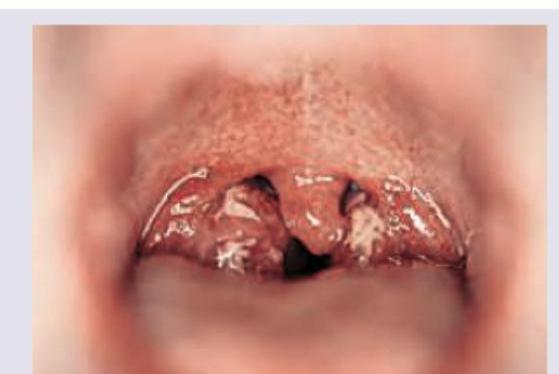

All are correct about the image shown below except:

Explanation: ***Uvula deviated to the affected side*** - In cases of **pharyngeal paralysis**, particularly involving the vagus nerve (CN X), the **uvula deviates *away* from the affected side** due to unopposed action of muscles on the healthy side. - Therefore, deviation to the affected side would be incorrect. *Nasal twang* - A **nasal twang** (or hypernasal speech) is a characteristic symptom of **palatal weakness**, where the soft palate cannot adequately close off the nasopharynx during speech, allowing air to escape through the nose. - This is consistent with a lesion affecting the ipsilateral vagus nerve. *Left-sided dropped palatopharyngeal arch* - The image clearly shows a **lower and more flattened appearance of the left palatopharyngeal arch** compared to the right, indicating weakness or paralysis of the muscles in that area. - This "dropped" appearance is a classic sign of **vagal nerve palsy**, affecting the muscles responsible for elevating the soft palate. *Ipsilateral loss of gag reflex* - The **gag reflex** is primarily mediated by the **glossopharyngeal nerve (CN IX)** for the afferent limb and the **vagus nerve (CN X)** for the efferent limb. - **Unilateral weakness of the soft palate**, as suggested by the dropped arch, is consistent with a lesion of the vagus nerve, which would result in loss of the gag reflex on the ipsilateral side.